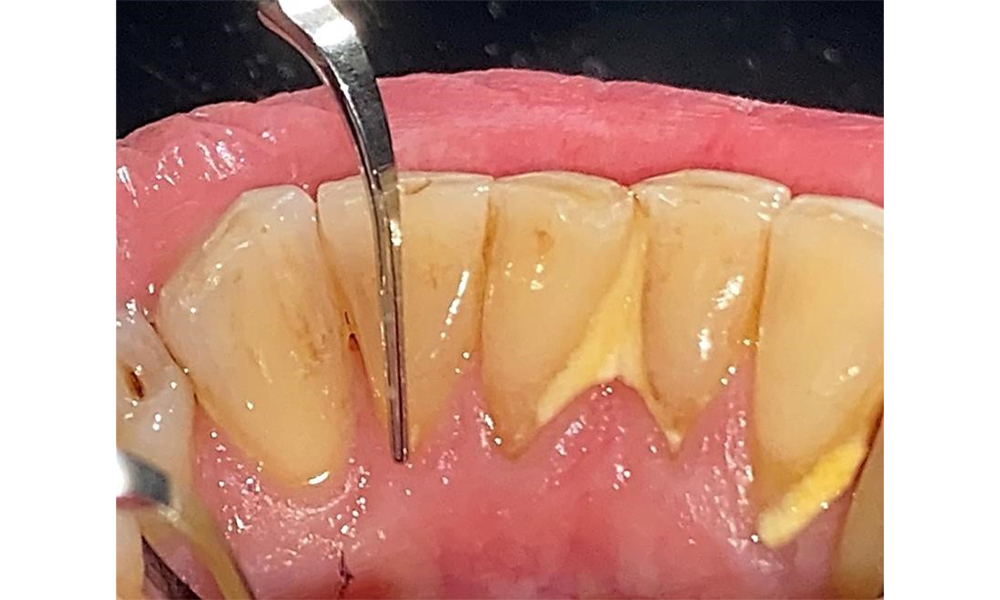

Frontal view with loss of the interdental papillae between 12 and 11.

Fig. 2 Frontal view with loss of the interdental papillae between 12 and 11. © Dr R. Krapf

The patient has stage II, grade B periodontitis (5). At 1 to 3 mm, the clinical probing depths were within the physiological range. Localized probing depths of 5 mm were observed on the mesiopalatal aspects on both 17 and 27. There are generalized recessions of 1–3 mm with partial loss of the interdental papillae (Fig. 2, Fig. 3, Fig. 4)

The documentation of periodontal findings, including pocket depth probing and bleeding status, is mandatory during each dental appointment due to the presence of periodontitis (Fig. 8). This will record the individual therapeutic needs and facilitate a rapid response to any progression of the pre-existing periodontitis.

Probing to document the findings in tooth 27 mesiopalatal. © Dr R. Krapf

Fig. 8: Probing to document the findings in tooth 27 mesiopalatal. © Dr R. Krapf